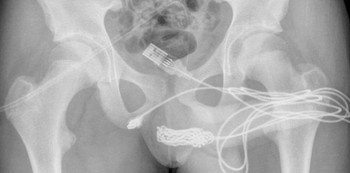

Image courtesy: University College Hospital London

X-rays revealed that there was a huge knot of USB cable inside the teenager, and surgeons managed to remove it by making an incision in the region between his genitals and anus.